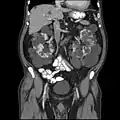

Polycystic kidneys

polycystic kidney, external surface with multiple cysts.

Cut surface of kidney showing multiple cysts with old and more recent haemorrhage.